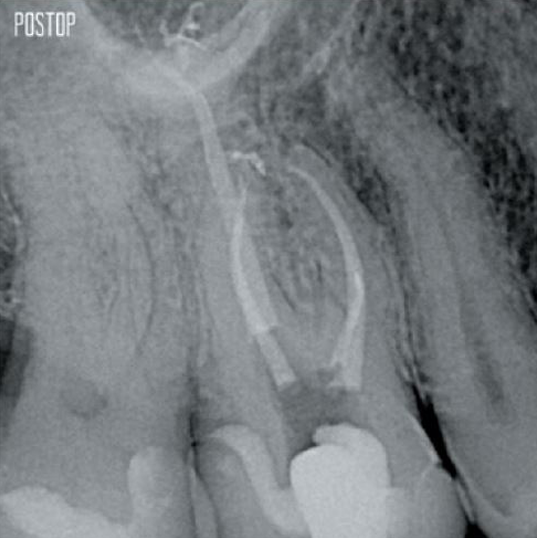

Fotos cortesía del Dr. Ahmed Salman

Más dentina conservada. Conformación, irrigación y obturación adecuadas.

El tratamiento satisfactorio del conducto radicular comienza con un acceso adecuado a la cámara pulpar. El procedimiento ideal proporciona acceso a los orificios de los conductos radiculares con una pérdida mínima de dentina.

Se recomienda una cavidad de endodoncia conservadora (CEC) con el sistema TruNatomy®.

El acceso ahora es posible desde diferentes ángulos, mientras que, hasta ahora, la estructura debía sacrificarse (cavidad de endodoncia tradicional).1

Sin necesidad de acceso en línea recta.1

La unión de la geometría de la lima, las conicidades regresivas y el alambre delgado y altamente flexible permite un tratamiento eficiente del conducto radicular al tiempo que se elimina solo la dentina cuando es clínicamente necesario.1